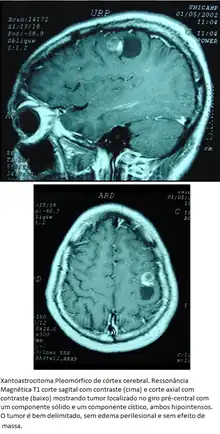

Xantoastrocitoma Pleomórfico

Tumor astrocitário raro, de crianças e adultos jovens, com localização superficial nos hemisférios cerebrais, envolvimento das meninges e prognóstico favorável. Tem aspecto pleomórfico, incluindo células tumorais lipidizadas que expressam GFAP (portanto, de linhagem astrocitária), que pode estar envolvidas por estroma reticulínico. Em relação à invasão de estruturas cerebrais, ocupam posição intermediária entre os astrocitomas pilocíticos e os difusos. Contudo, podem ter feições histológicas agressivas.

Localização. Preferência pelo lobo temporal. O tumor é cortical, estendendo-se da leptomeninge à transição com a substância branca. As bordas são nítidas em TC e RM, com tendência à formação de cistos com nódulo mural. Há captação de contraste.

Morfologia. São aderidos às leptomeninges. Há componentes sólido e cístico. O nódulo mural é amarelo-alaranjado e mais firme que o cérebro. Microscopicamente, observam-se astrócitos pleomórficos gigantes, mono- ou multinucleados, com grande variação no tamanho e cromatismo dos núcleos (daí o adjetivo pleomórfico) misturados a células pequenas, poligonais ou fusiformes, GFAP-positivas e arranjadas em fascículos. O termo xantoastrocitoma é devido a que muitas células, especialmente as maiores, mostram acúmulo de gotículas lipídicas. A celularidade é moderada, mas pode ser focalmente alta. Mitoses e necrose são raras ou ausentes. Embora o tumor apareça macroscopicamente bem delimitado, pode haver invasão do cérebro e de espaços perivasculares. Em impregnações pela prata, fibras reticulínicas podem ser abundantes e circundar individualmente células tumorais. Em microscopia eletrônica, as células são envoltas por membrana basal, uma feição também encontrada em astrócitos subpiais normais. Por isto, foi postulada origem nestes. A consistência firme é atribuída ao estroma reticulínico, mais proeminente onde há envolvimento leptomeníngeo.